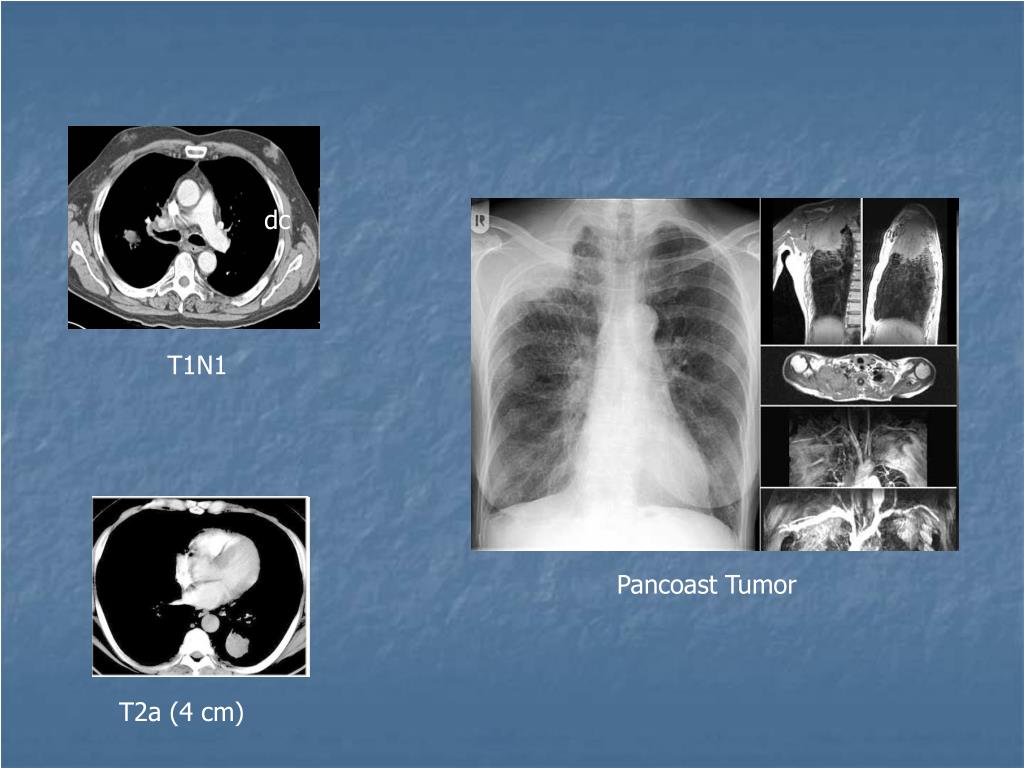

35. dc T1N1 Pancoast Tumor T2a (4 cm)